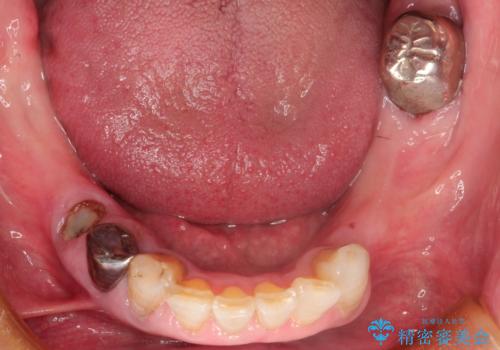

下顎の両側の奥歯が欠損しており、入れ歯をお持ちでしたが、うまく咬めずにほとんど使用していない状態でした。

上顎は全体的にクラウンの入れ替えと、下顎はインプラントの提案もしましたが、希望されなかったのでノンクラスプデンチャーの製作をする治療計画としました。

お忙しい方でしたので、治療が終了するまでにじかんがかかってしまいましたが、奥歯でもしっかり咬めるようになったと喜んでいただけました。